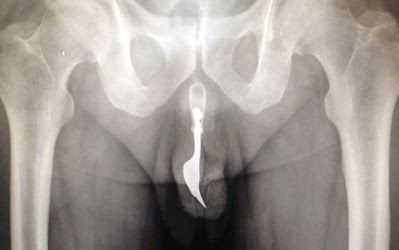

Doktor di Canberra, Australia baru-baru ini berjaya mengeluarkan garpu besi sepanjang 10 sentimeter dari kemaluan seorang lelaki yang memasukkan benda asing itu, kononnya untuk menikmati cara baru keseronokan seks Lelaki berusia 70 tahun itu mengunjungi jabatan kecemasan Hospital Canberra mengadu kemaluannya berdarah.

Dia mengaku memasukkan garpu itu ke dalam uretranya. Malangnya, keseronokan yang diimpikan menjadi mimpi ngeri baginya apabila garpu berkenaan tersekat menyebabkan dia mengalami kesakitan melampau. Meskipun begitu, dia mengambil masa hingga 12 jam sebelum membuat keputusan untuk mendapatkan bantuan perubatan.

Menurut laporan dalam keluaran terbaru Jurnal Pembedahan Antarabangsa, garpu itu tersekat begitu teguh di dalam kemaluan mangsa hingga doktor berdepan dengan kesukaran untuk mengesannya.

Sebaik berjaya menentukan kedudukannya, pelbagai cara digunakan untuk mengeluarkan garpu itu dan akhirnya berjaya selepas mengguna forsep serta pelincir yang banyak.